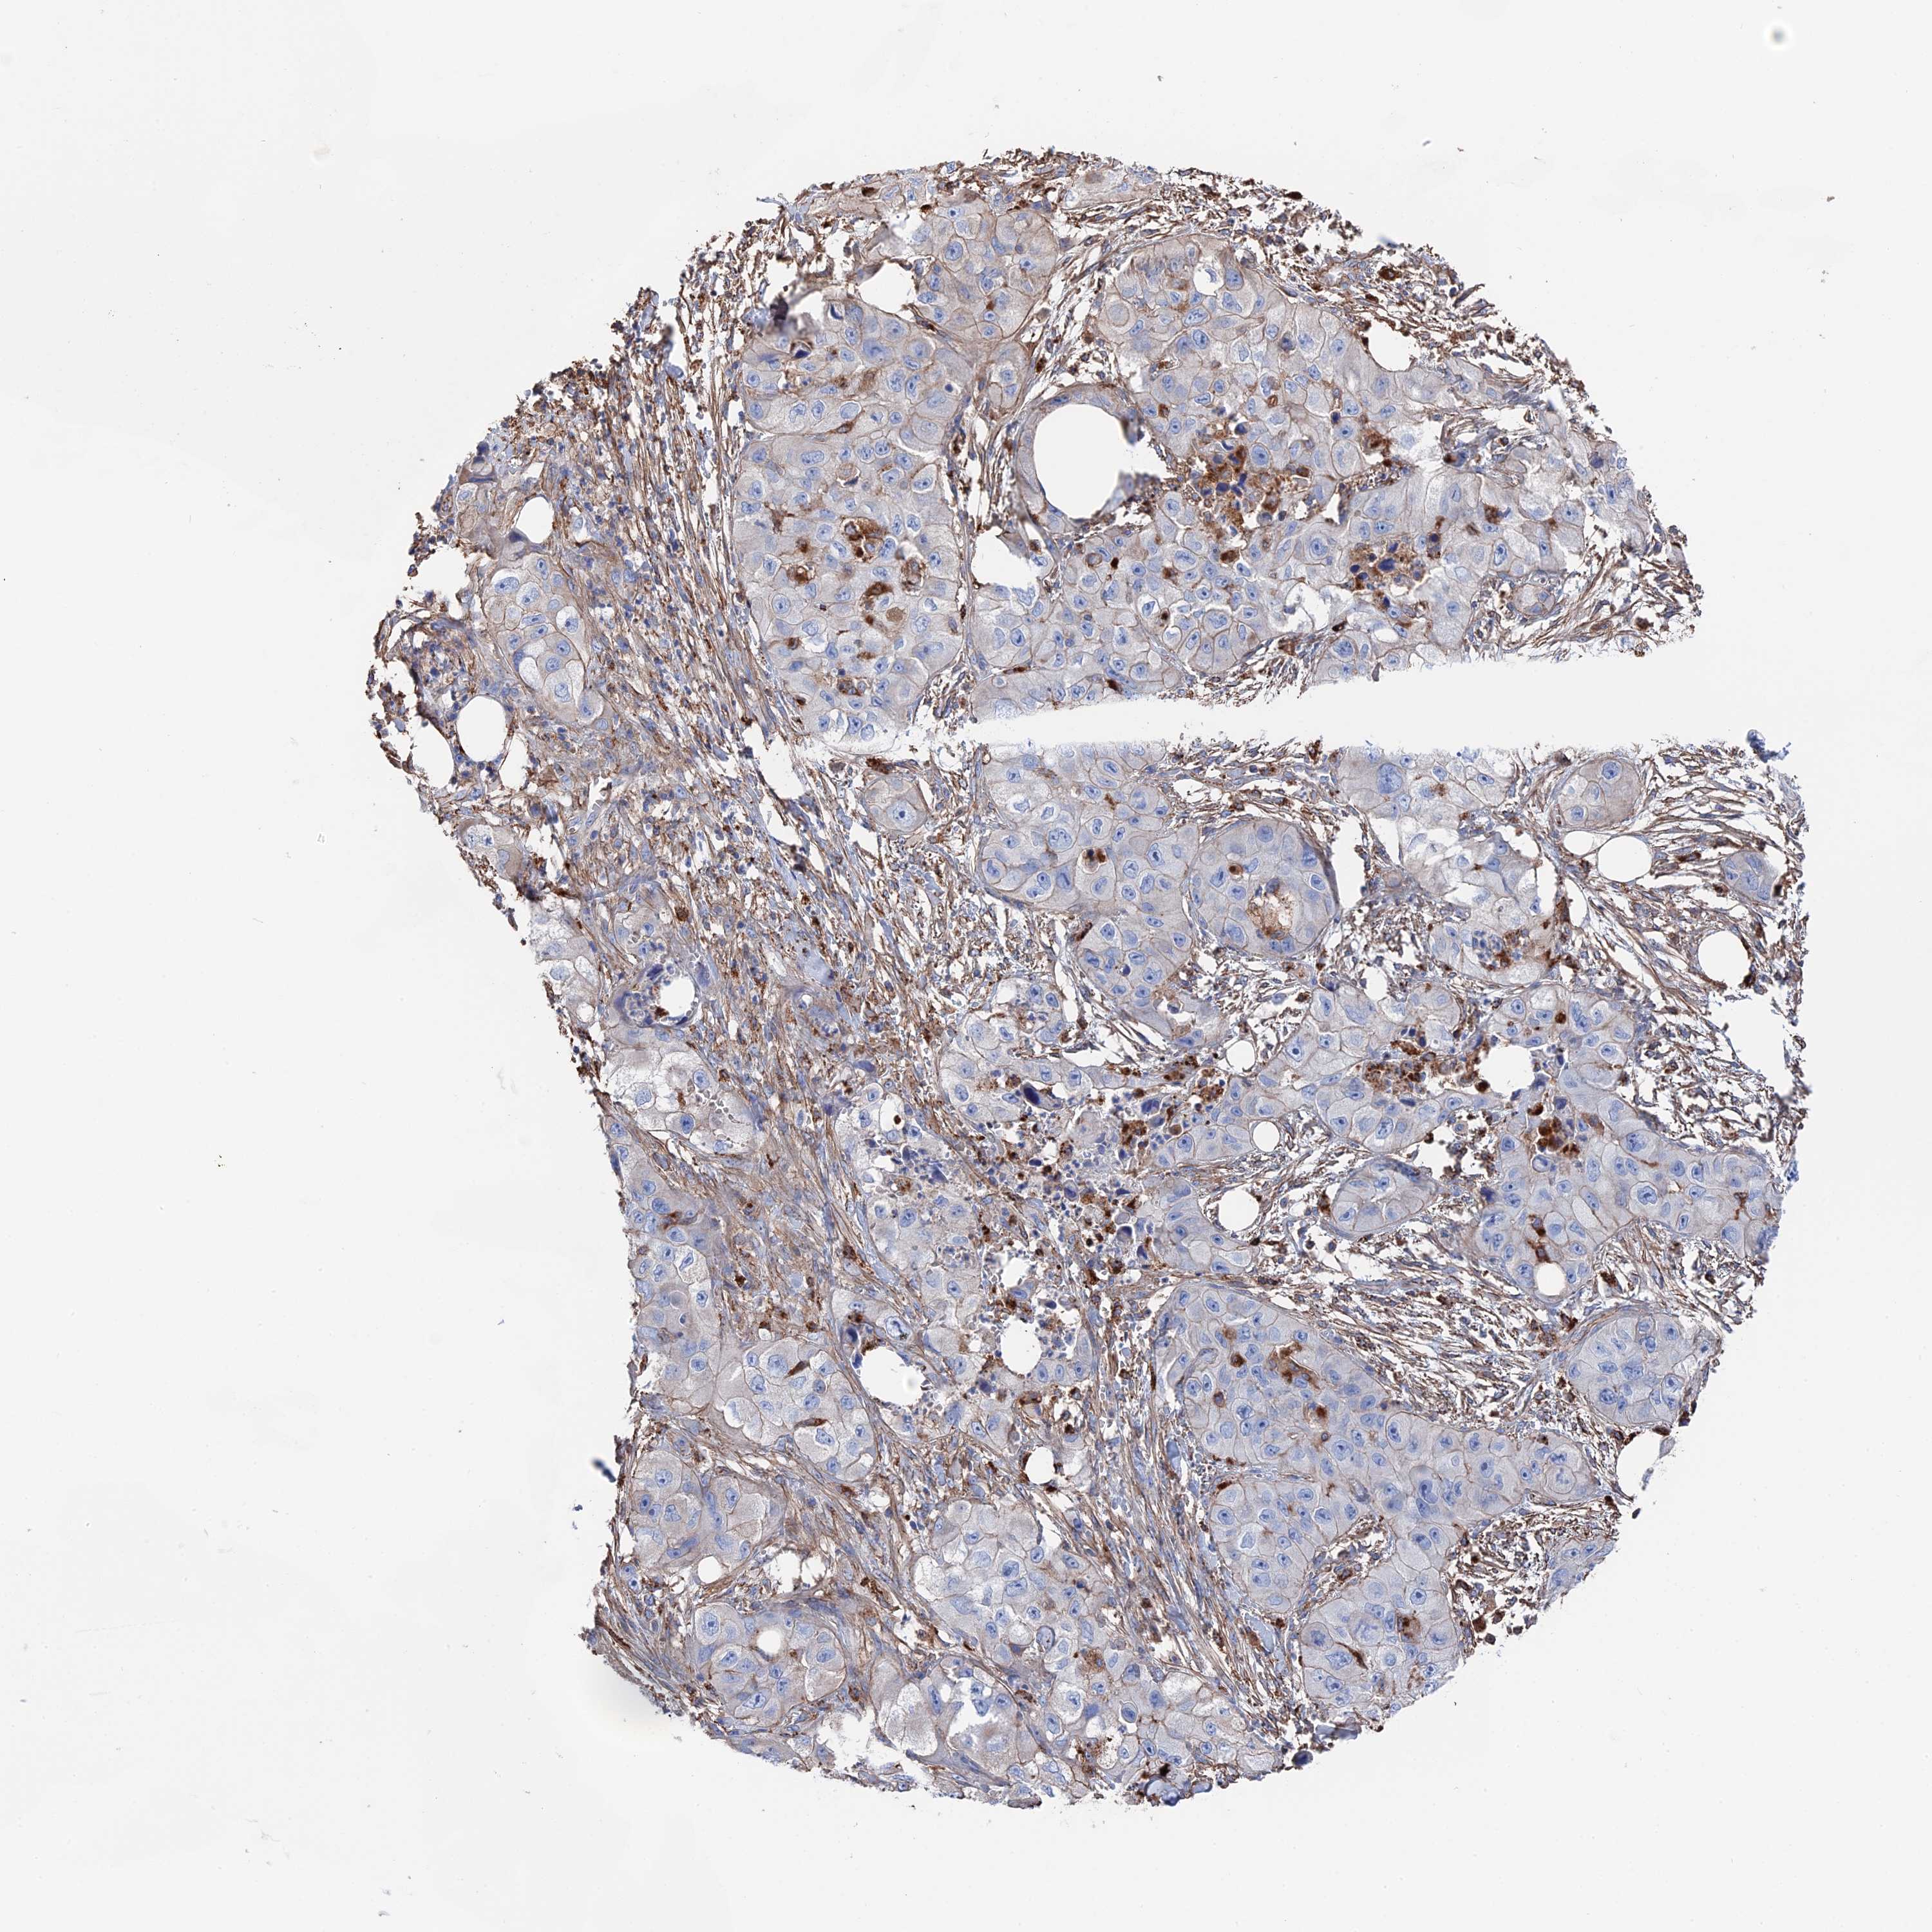

Basal cell and squamous cell cancer

SKIN CANCER - Protein expressioni

A mouse-over function shows sample information and annotation data. Click on an image to view it in a full screen mode. Samples can be filtered based on level of antibody staining by selecting one or several of the following categories: high, medium, low and not detected. The assay and annotation is described here.

Each image is clickable and will lead to virtual microscopy that enables deeper exploration of all samples and also displays staining intensity scores, fraction scores and subcellular localization as well as patient and tissue information for each sample.

Antibody HPA040839

Staining

High

Intensity

Strong

Quantity

>75%

Location

Nuclear

Basal cell carcinoma